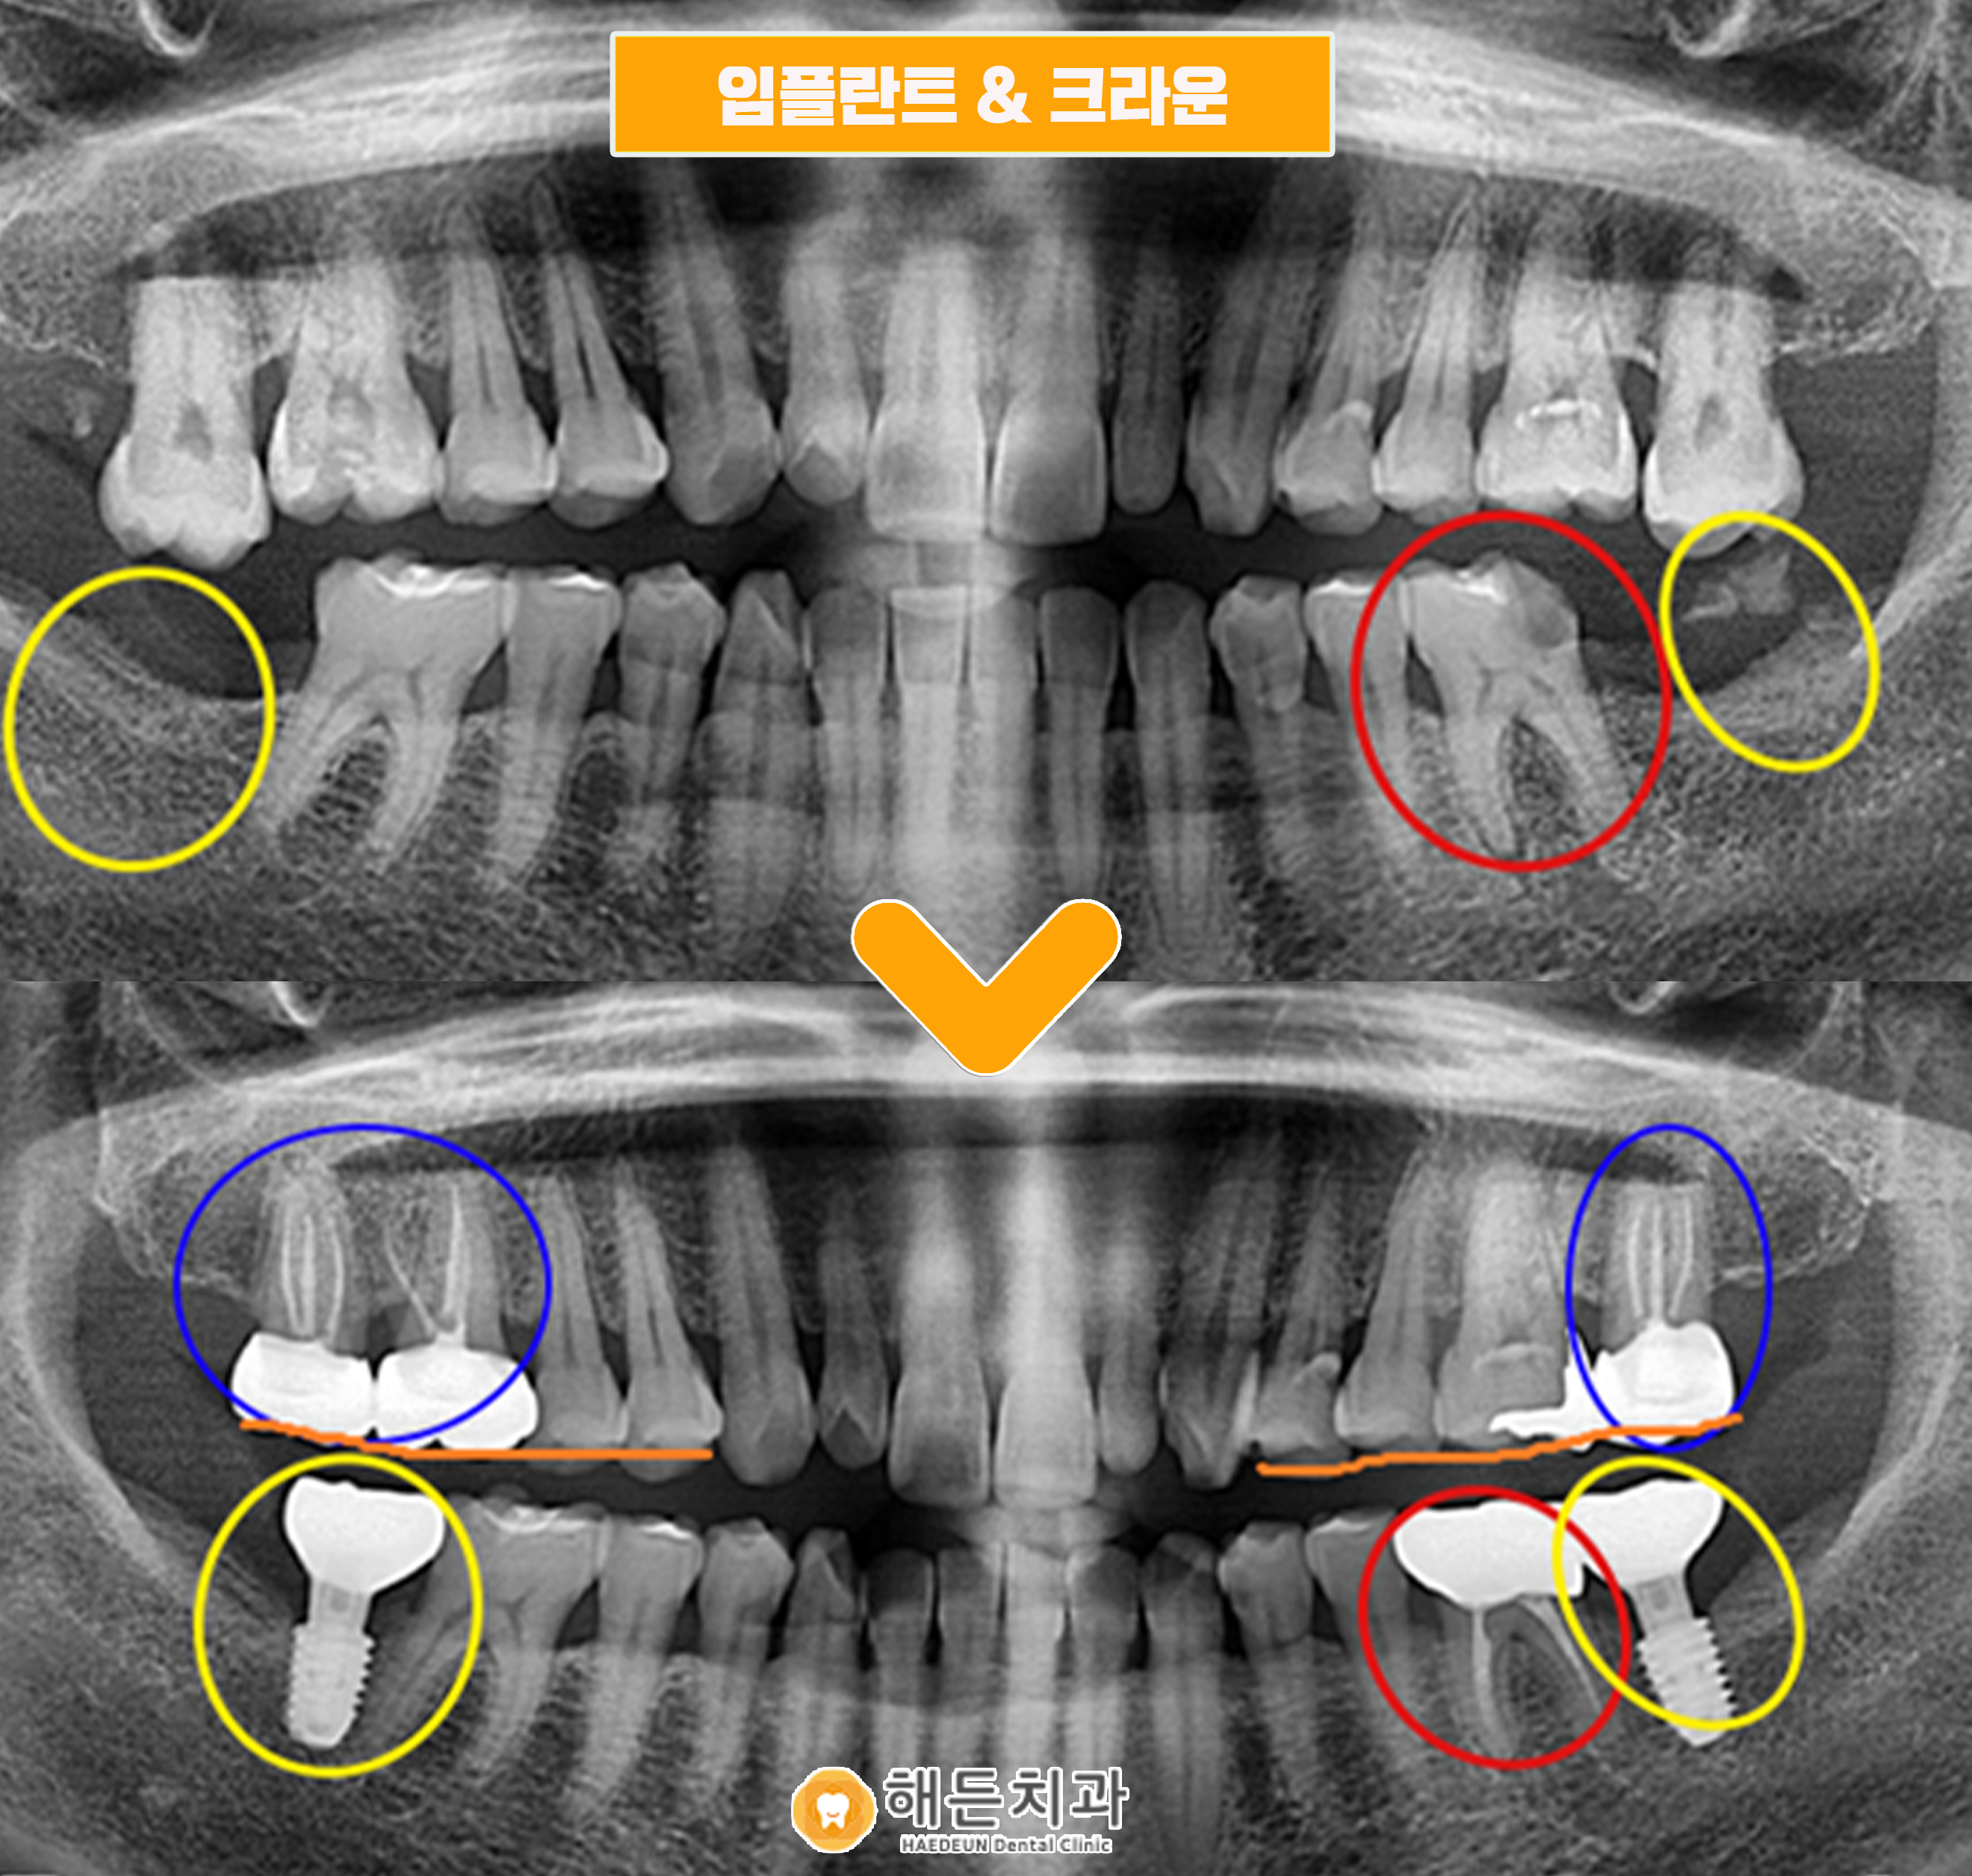

천안아산치과 해든치과에서 치료를 받은 후 사진입니다.

양측 아래 최후방 어금니자리에 임플란트 치료를 완료하였고,

충치가 있던 왼쪽 아래 어금니는 신경치료 및 크라운 치료를 완료하였습니다.

그리고 위의 정출된 치아들을 옆에 치아들과 높이를 맞추며, 신경치료 및 크라운치료를 진행했습니다.

.

추가적으로 불편했던 오른쪽 위 첫번째 큰 어금니도 같이 신경치료 및 크라운을 진행했습니다.

임플란트치료 및 신경치료와 크라운치료를 통해 환자분의 불편감을 해소시켜 드렸으며, 다음 정기 검진 때 뵙기로 하였습니다.